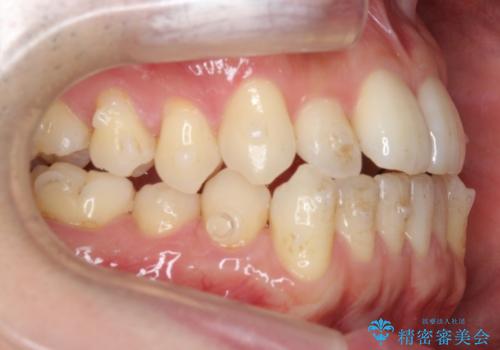

前歯の反対咬合でしたが、かみ合わせが、下顎が大きく前方にずれていました。

引っ込んでいる前歯の前方に下の犬歯が深く咬み込んでおり、また、奥歯のかみ合わせも受け口方向にずれ、骨格性の反対咬合も少々ありました。

上の前歯を前方に出すだけでは治療ができないため、ミニスクリューを用いて下の奥歯を後ろに送っています。

また、下の前歯を0.3mmずつIPRしています。